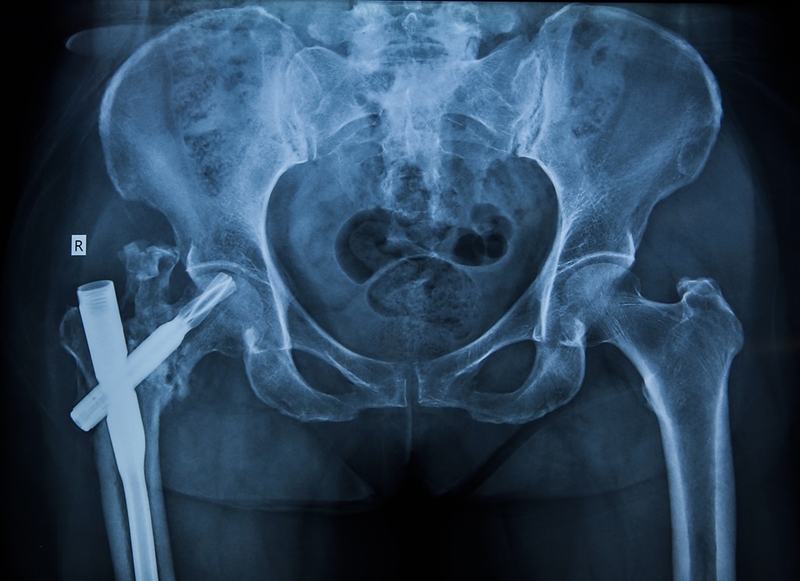

Đối với khớp háng là khớp có cấu trúc cũng như chức năng phức tạp. Những bệnh lý có liên quan đến khớp háng bao gồm viêm khớp, chấn thương, tổn thương xương, thoái hóa khớp, hoại tử khớp, u… Những khảo sát hình ảnh để phát hiện bệnh lý khớp háng là chụp X quang hoặc chụp cắt lớp vi tính, chụp cộng hưởng từ. Chụp cộng hưởng từ MRI giữ vai trò hết sức quan trọng giúp đánh giá cấu trúc phần mềm cấu tạo khớp háng như sụn khớp, bao khớp, cơ quan vận hành khớp háng, tủy xương…